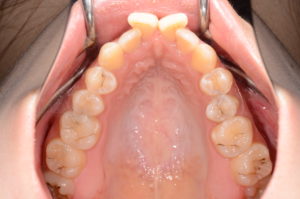

上の歯列がキュッとV字に細くなっている――。

結果、歯列は横幅を失い、上あごがV字にすぼまっていきます。

✅上の歯列はU字よりV字に見える?

V字の歯並びは、舌の位置・飲み込み方・唇や頬の力が大きく関係します。